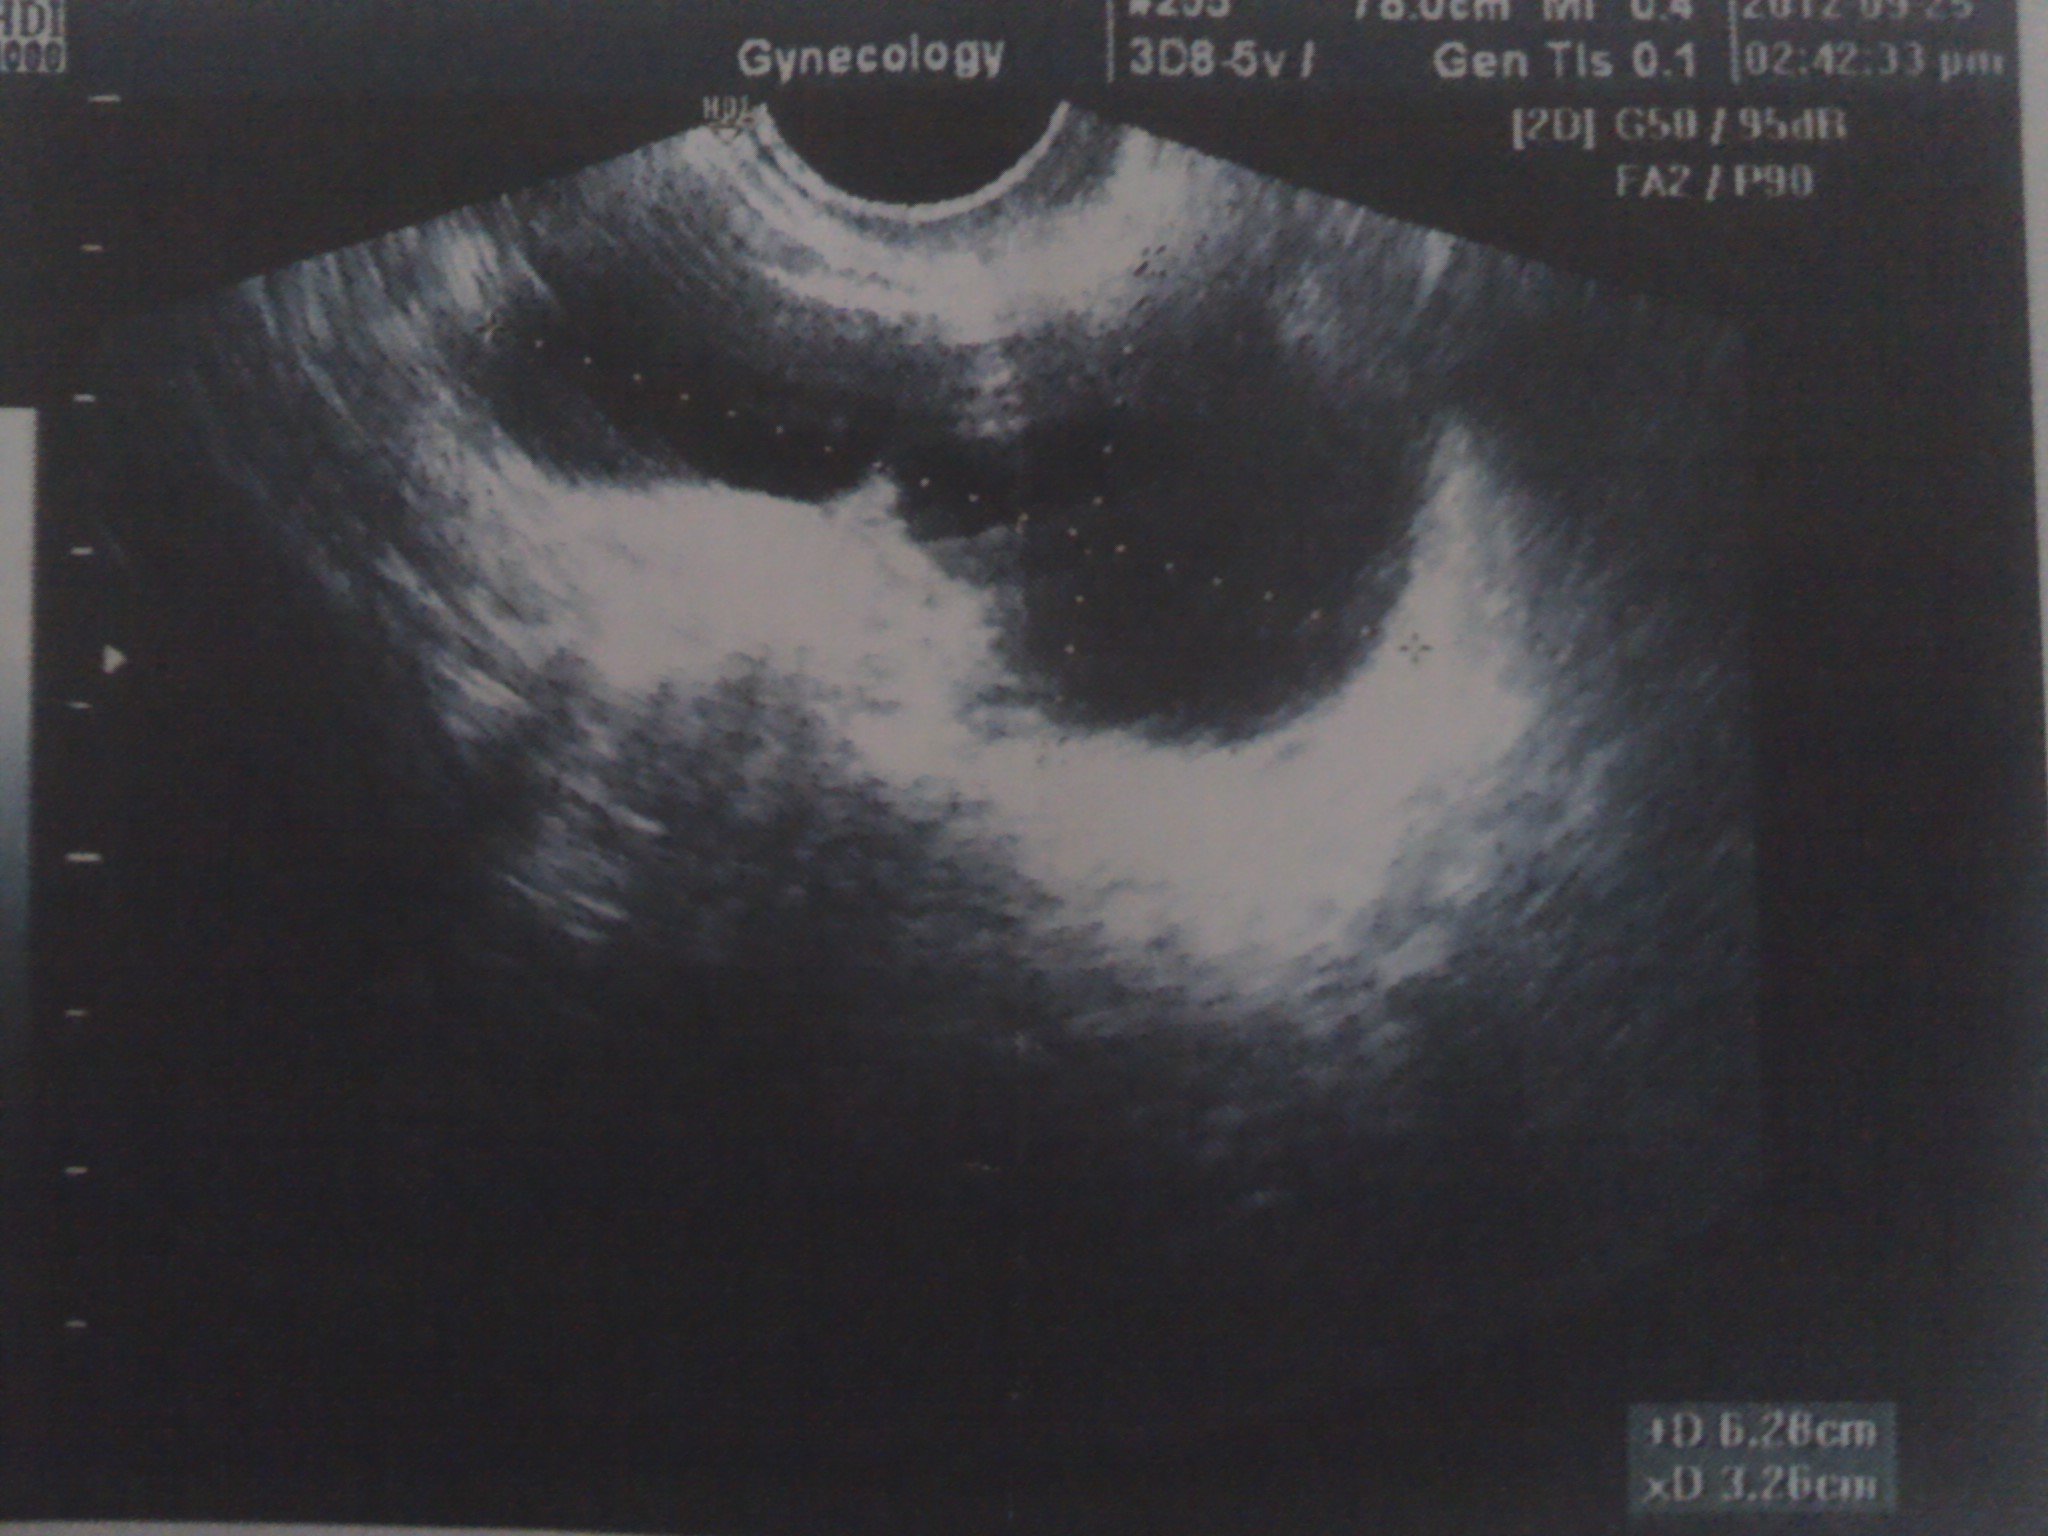

患者信息:女 31岁 辽宁 本溪 病情描述(发病时间、主要症状等):图1,图2,图3,是2012年6月30日拍的。超声所见:子宫前位,大小约4.6*3.6*3.6cm,肌层回声均匀。内膜厚约0.6cm。 左侧卵巢大小约2.5*2.1cm,内见2.4*2.0囊性暗区。 右侧卵巢大小约3.8*3.7cm囊性暗区,囊壁光滑,囊液透气好。诊断意见:左卵巢囊性结构,右卵巢囊肿—————————————————————————————————图4,图5,图6 是2012年9月25日拍的超声描述:子宫体大小约:3.8*3.9*2.8cm 子宫前位,轮廓清晰,光滑,肌层回声均匀,内膜厚约0.6cm 左卵巢大小约:3.2*1.6cm,右卵巢大小约:2.6*1.8cm,双附件区均可见无回声团,形态不规则,大小分别约5.8*2.9*3.5cm(左侧),6.2*3.2*3.4cm(右侧) 宫颈厚约2.2cm,回声较均匀。超声提示:双侧附件区囊性包快(考虑输卵管积液)想得到怎样的帮助:未婚,打算要孩子。这两次检查相差三个月,之前检查,都没说有输卵管积液。这次医生态度很严肃,说输卵管造影和通水现在都没用了。让我做腹腔镜,考虑试管婴儿。我的情况非常严重吗?怎么治疗?能看出我是哪种囊肿吗曾经治疗情况及是否有过敏、遗传病史:没治疗过。